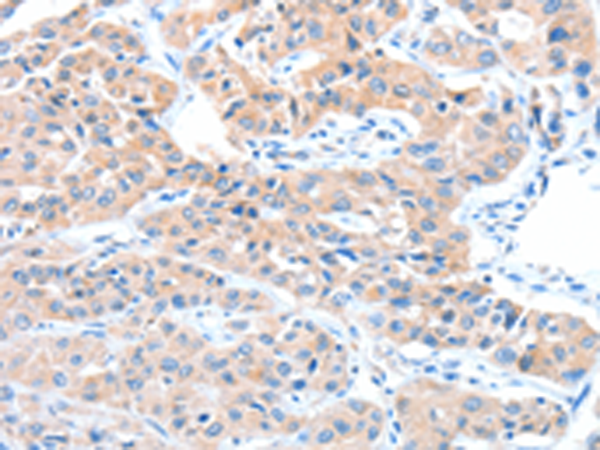

分类: 科研抗体货号: P07772别名:应用: WB,IHC反应种属: Human